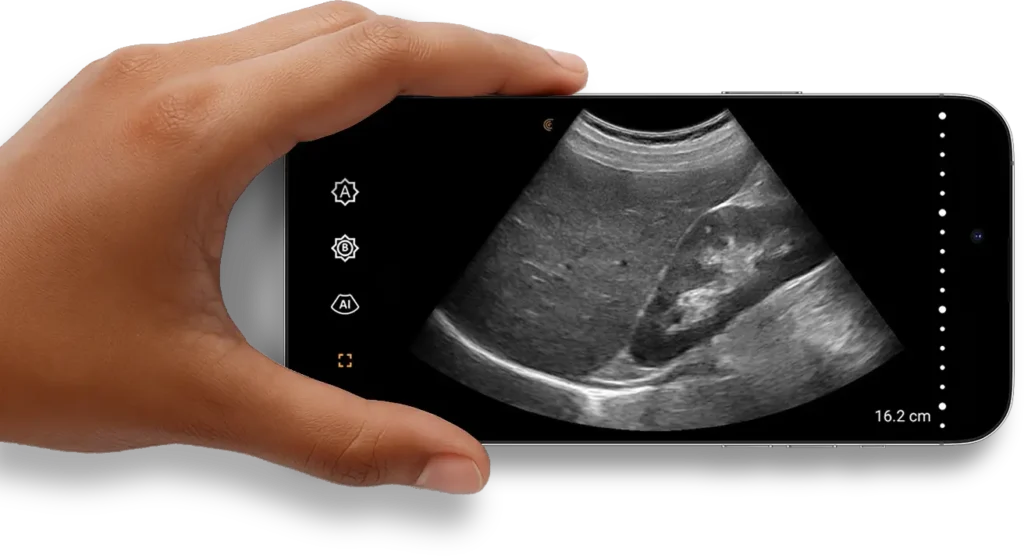

Your phone and Clarius are all you need to take the power of ultrasound with you wherever you go.